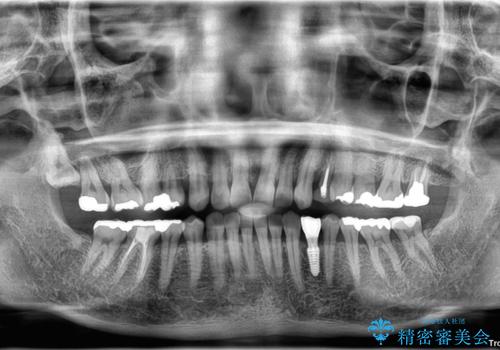

治療は計画通りに進み、約3か月で最終補綴まで完了。

見た目だけでなく、しっかり噛める機能も回復し、患者様にも大変ご満足いただけました。